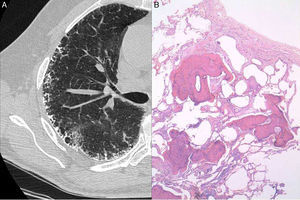

A 63-year-old man with a history of mild cigarette smoking and no other relevant conditions was under study in our Unit of Interstitial Lung Diseases for telomere shortness as a first grade relative of a patient with IPF. His brother suffered from IPF, and both patients were diagnosed with telomere shortness (<1%) after genetic processing of a mouth swab specimen. He had no respiratory symptoms. Chest radiography showed bilateral peripheral reticulo-nodular pattern. Pulmonary function tests showed a mild restrictive pattern with forced vital capacity (FVC) of 3.83L (79%), total lung capacity (TLC) of 6.43L (85%) and carbon monoxide transfer coefficient (KCO) 4.82 (125%). No oxygen desaturation was seen in the 6-minute walking test. Laboratory data including hematological tests, coagulation, and renal and liver functions were normal. Serum precipitins for different common antigens (avian and fungi) were negative, as were immunological investigations, including rheumatoid factor, antinuclear antibodies and antineutrophil cytoplasmic antibodies. A high-resolution CT chest scan demonstrated profuse calcification within the reticular (septal) lines (Fig. 1A). A surgical lung biopsy of the upper and lower left lobules was performed. Histology showed numerous foci of branching bone tissue, some of them with associated marrow elements, and marked fibrosis of neighboring interstitium with abundant fibroblastic foci, consistent with DPO and probable UIP pattern (Fig. 1B).